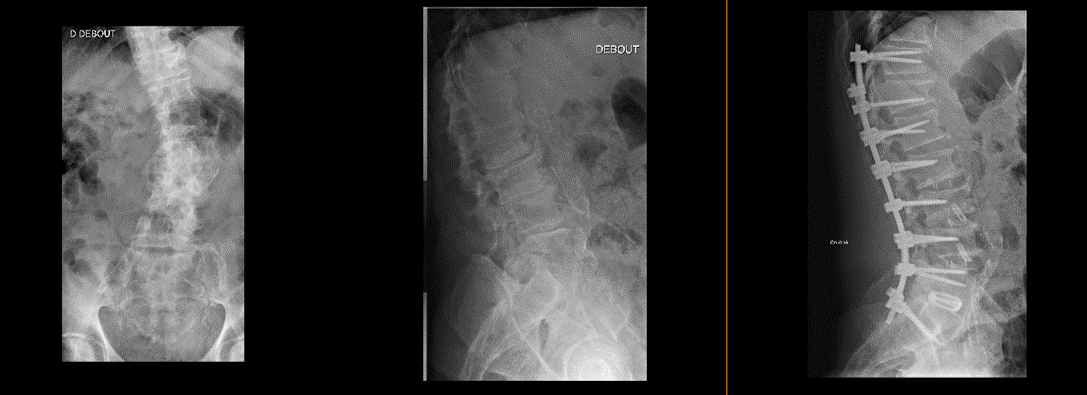

Radiographie pré et post opératoire d’une arthrodèse pour correction de scoliose